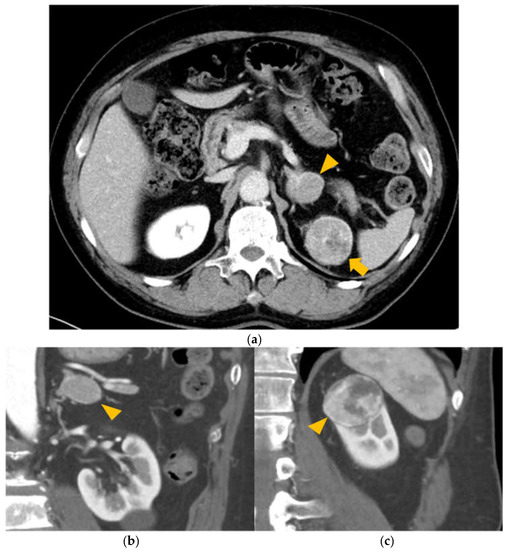

2.1. Case Description, Timeline, and Clinical Intervention